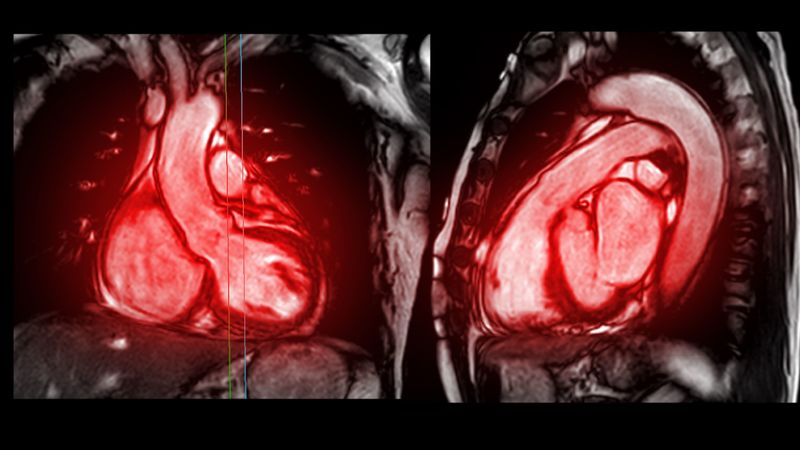

2019年11月、「ステントグラフト」という人工血管を挿入する手術以降、定期的に通院していた母親は、血液検査や尿検査の結果、腎機能が弱くなっていることを指摘される。

母親はこの他にも、半年に1回、大動脈瘤やリンパ腫などの予後の確認のため、総合病院でCT検査を受けていただけでなく、皮膚科や整形外科などの受診が必要になることも。その際は、冬木さんが建設会社の派遣の仕事の休みを取って付き添っていた。